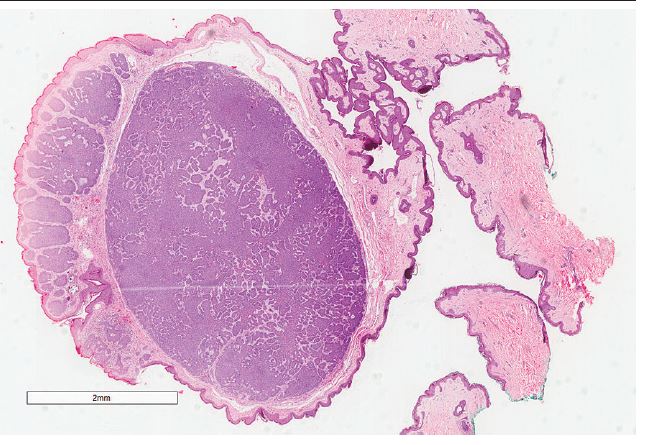

A 67-year-old female patient presented with a pedunculated normochromic lesion in the abdomen (Figure 1) of unknown evolution together with multiple benign lesions such as intradermal nevi, rubi angiomas and soft fibromas. Dermoscopy with polarized light surprisingly evidenced the presence of ovoid nests, focused arboriform vessels and chrysalis (Figure 2), findings highly suggestive of basal-cell carcinoma (BCC), and the lesion was excised. Histopathology revealed an asymmetric polypoid tumor containing aggregations of atypical basaloid cells present in a palisade restricted to the polypoid area, incorporated into the fibrinoid stroma and separated by focal fissures (Figure 3).

BCC: basal-cell carcinoma; HE: hematoxylin and eosin.